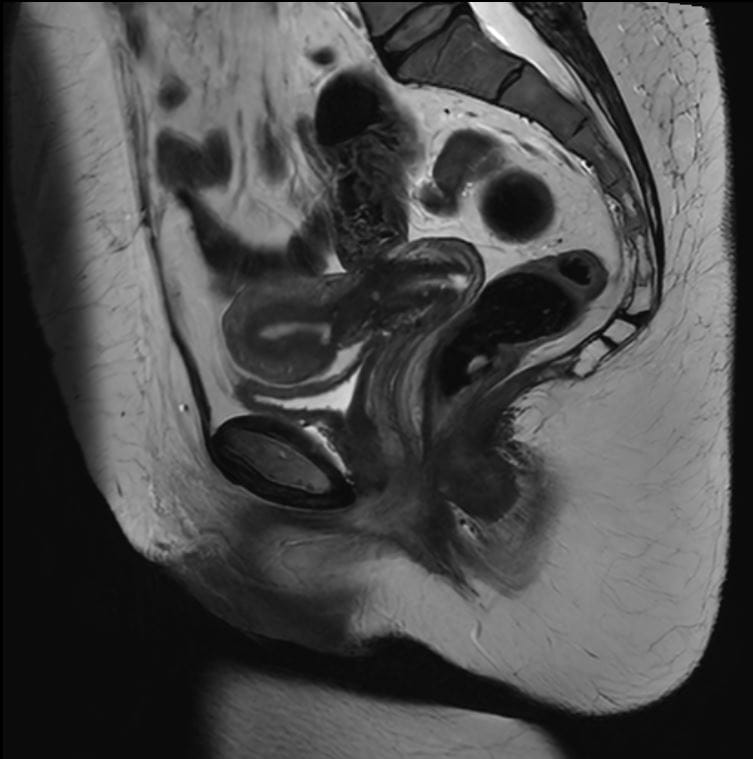

Eksempler på MR Scanninger

En gynækologisk MR-scanning af kvindelige kønsorganer er en skånsom og præcis undersøgelse, der giver detaljerede billeder af underlivet. Vores 3 tesla MR-scanner bruger et magnetfelt og radiobølger til at skabe tydelige billeder af bløddele som livmoder, æggestokke og omkringliggende væv – helt uden brug af røntgenstråling.

Denne type undersøgelse er særligt god til at undersøge og diagnosticere forskellige tilstande i underlivet, der kan være svære at opdage med andre metoder. MR-scanning kan give et klart og detaljeret billede af eventuelle forandringer eller sygdomme i de kvindelige kønsorganer.